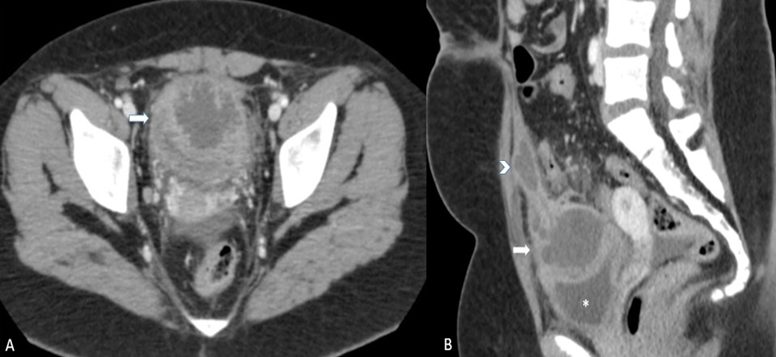

To further investigate the pelvic findings, a Contrast Enhenaced Computed Tomography (CECT) scan was performed two days later. The CT scan revealed an oval, hypoattenuating formation with irregularly thickened walls, with contrast enhancement after contrast medium injection suggestive of an abscess (Figure 2).

Figure 2: Contrast Enhanced CT: A) Axial scan: supravesical cystic structure with irregular thickening and contrast enhancing of the walls. B) Sagittal MPR reconstruction well depict communication of the cystic mass (white arrow) with another hypoattenuating structure, extending beneath the abdominal wall to the subumbilical region and corresponding to a fluid-containing urachal remnant (head arrow). The bladder was impressed from the cystic mass (asterisc).

This formation was comunicating with another hypoattenuating structure, extending beneath the abdominal wall to the subumbilical region for approximately 55 mm ad corresponding to a fluidcontaining urachal remnant. It also exerted an impression on the upper wall of the bladder, without a well-defined cleavage plane, and demonstrated wall thickening. The CT scan also indicated no clear cleavage plane with the right wall of the sigma colon (in the context of dolichosigma), which exhibited wall thickening. Additionally, the pelvic cavity appeared imbibed and engorged, with several centimeter-sized lymph nodes identified. A small amount of free fluid was present in the pelvic cavity and the right iliac fossa.